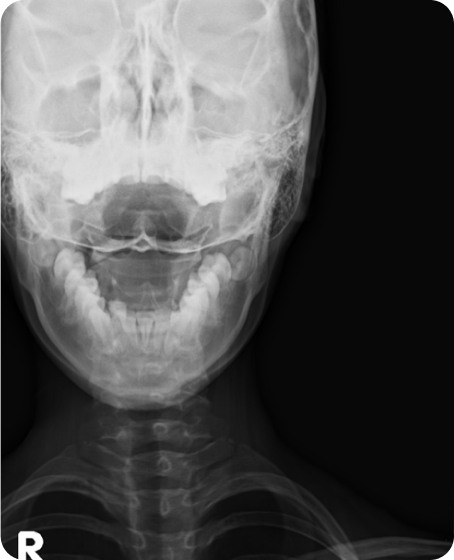

▲ CTA 9개월 착용 (2016년 10월 29일)